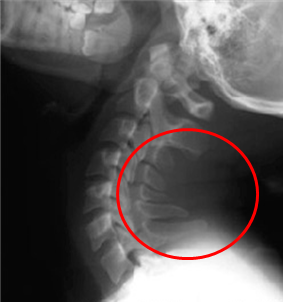

목뼈의 뒤쪽에는 spinous process라는 꼬리처럼 생긴 극돌기가 있습니다. 그림의 빨간 동그라미 보이시죠? 거북목일 경우 이 극돌기끼리 더 가깝게 붙어있는 경우가 많습니다.

머리를 과도하게 젖히게 되면 이 극돌기끼리 부딪치면서 통증이 생길 수 있습니다. 거북목을 가지신 분들이 과도하게 목을 젖히는 스트레칭을 할 경우 이 같은 이유로 더욱 통증이 심해질 수 있습니다.